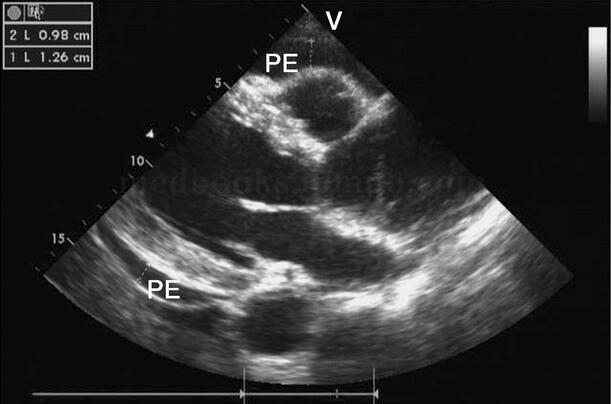

图2‐1‐228 大量心包积液

A﹒显示心尖部积液,厚度达35mm;B﹒左室短轴切面;C﹒大量心包积液使右室前壁受压塌陷;D﹒大量心包积液使右房壁受压塌陷PE:心包积液